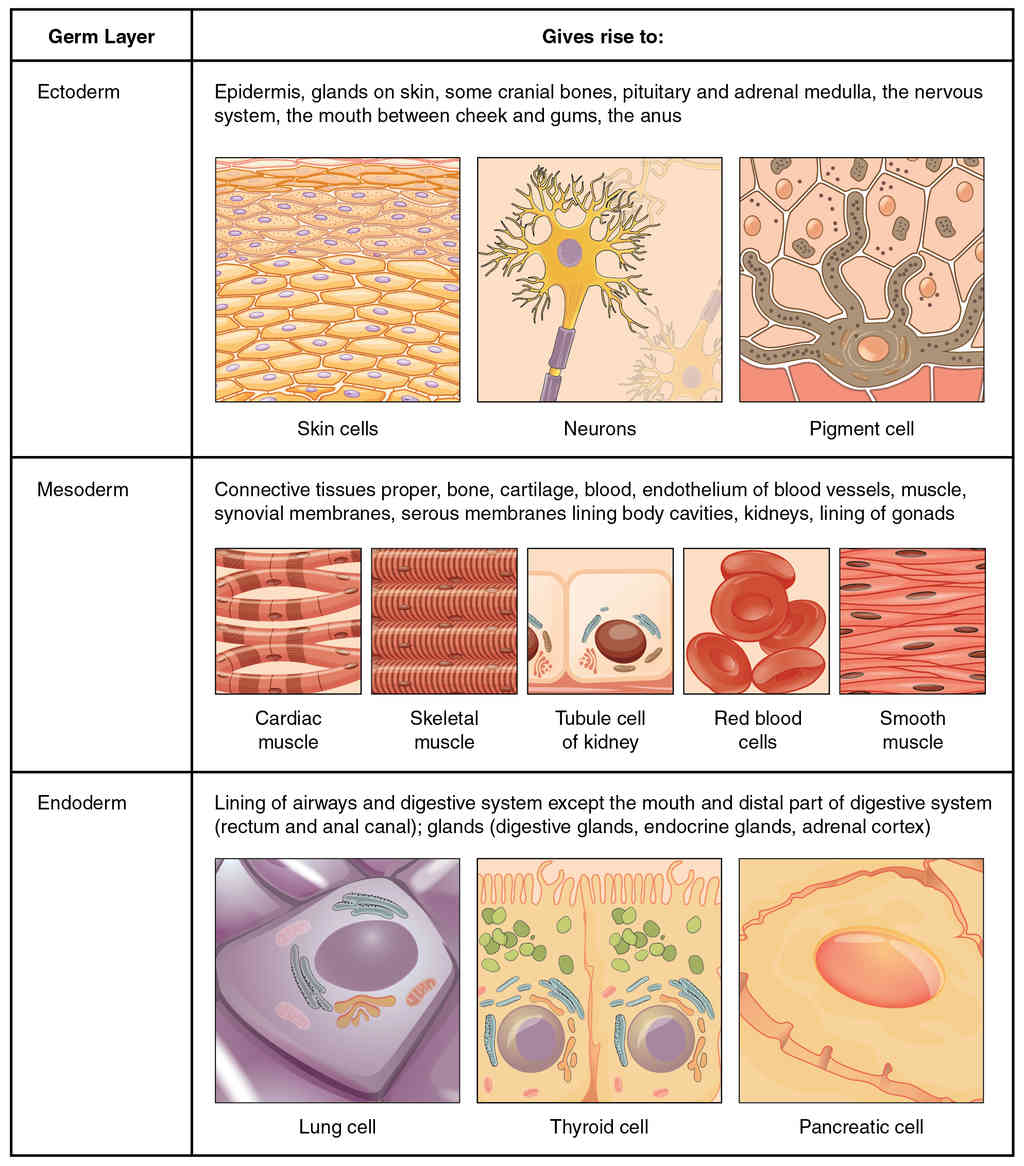

This page is under construction. For now, it is just a resource of the images found in the OpenStax Anatomy and Physiology Handbook. It wil slowly change into a revision tool. Each slide has a number. Use this to refer to the slide. When completed, it will have an unlabelled section, with labelled slides in parallel. On the unlabelled slides, write your answer and use the labelled slide to assess yourself. Keep track by also noting the number on each slide. Improvement at each attempt is important, more so than full marks on a first attempt.